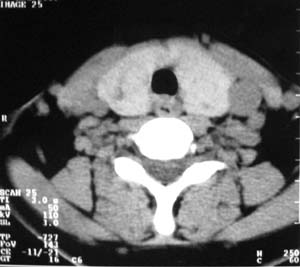

以下是引用zsl6918在2007-8-27 14:40:00的发言:[br]双侧甲状腺多发性低密度占位,边界清晰,密度欠均匀,尤以左侧明显,与周围组织分解清,考虑多发性腺瘤可能性大,不除外结节性甲状腺肿

以下是引用liaizhi在2007-8-27 15:20:00的发言:[br]双侧甲状腺散在多个囊性第密度影,左侧最大一个病灶与正常甲状腺分界尚可,气管受压稍右移。考虑甲状腺瘤的可能性大。